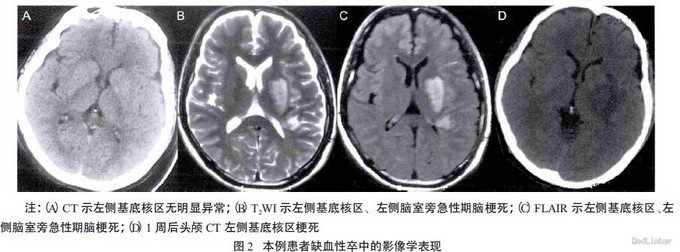

体格检查:体温36.7 ℃,脉搏73 次/分,呼吸18 次/分,血压140/100 mmHg。。神经系统查体:神清,构音不清,伸舌偏右,右侧肢体肌张力 低,右侧肌力Ⅳ级,腱反射对称存在(++)。辅助检查:头颅CT 示:左中央前沟局限性高密度影,见图1A,左侧基底核区无异常,见图2A。颈动脉彩超示:左侧颈内动脉血流信号及频谱异常;左侧颈总动脉阻力指数增高。

予改善循环、护脑等治疗。1 d 后病情加重:右侧肢体无法上抬,右侧肢体肌力Ⅰ~Ⅱ级。行头颅MRI 示左侧基底核区、左侧脑旁急性期脑梗死,见图2B-C,左中央前沟局限性出血信号,见图1B。为进一步诊治转诊华中科技大学同济医学院附属同济医院神经内科。发病第5 天,头MRI 的磁敏感加权示左顶叶中央前沟内线形低信号,见图1C;CTA示左侧颈内动脉C1-C4 段狭窄闭塞,见图1D。治疗上给予波立维75 mg 和阿司匹林100 mg抗血小板聚集、瑞舒伐他汀钙20 mg 强化降脂,同时应用尤瑞克林、依达拉奉和奥拉西坦等治疗。诊断:蛛网膜下腔出血。

1 周后复查头颅CT 示左侧基底核区梗死、左顶叶中央前沟高密度影较前明显降低,见图1E、2D。2 周后,患者右上肢肌力恢复至Ⅲ级、下肢肌力恢复至Ⅳ级,3 月后改良Rankin 量表评分为2分。---摘自神经损伤与功能重建。